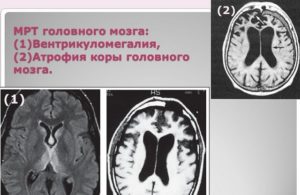

- Для диагностики взрослого человека назначается МРТ головного мозга.

Все процедуры направлены на обследование желудочков головного мозга и выявление латеровентрикулоасимметрии (нарушение симметрии желудочков).